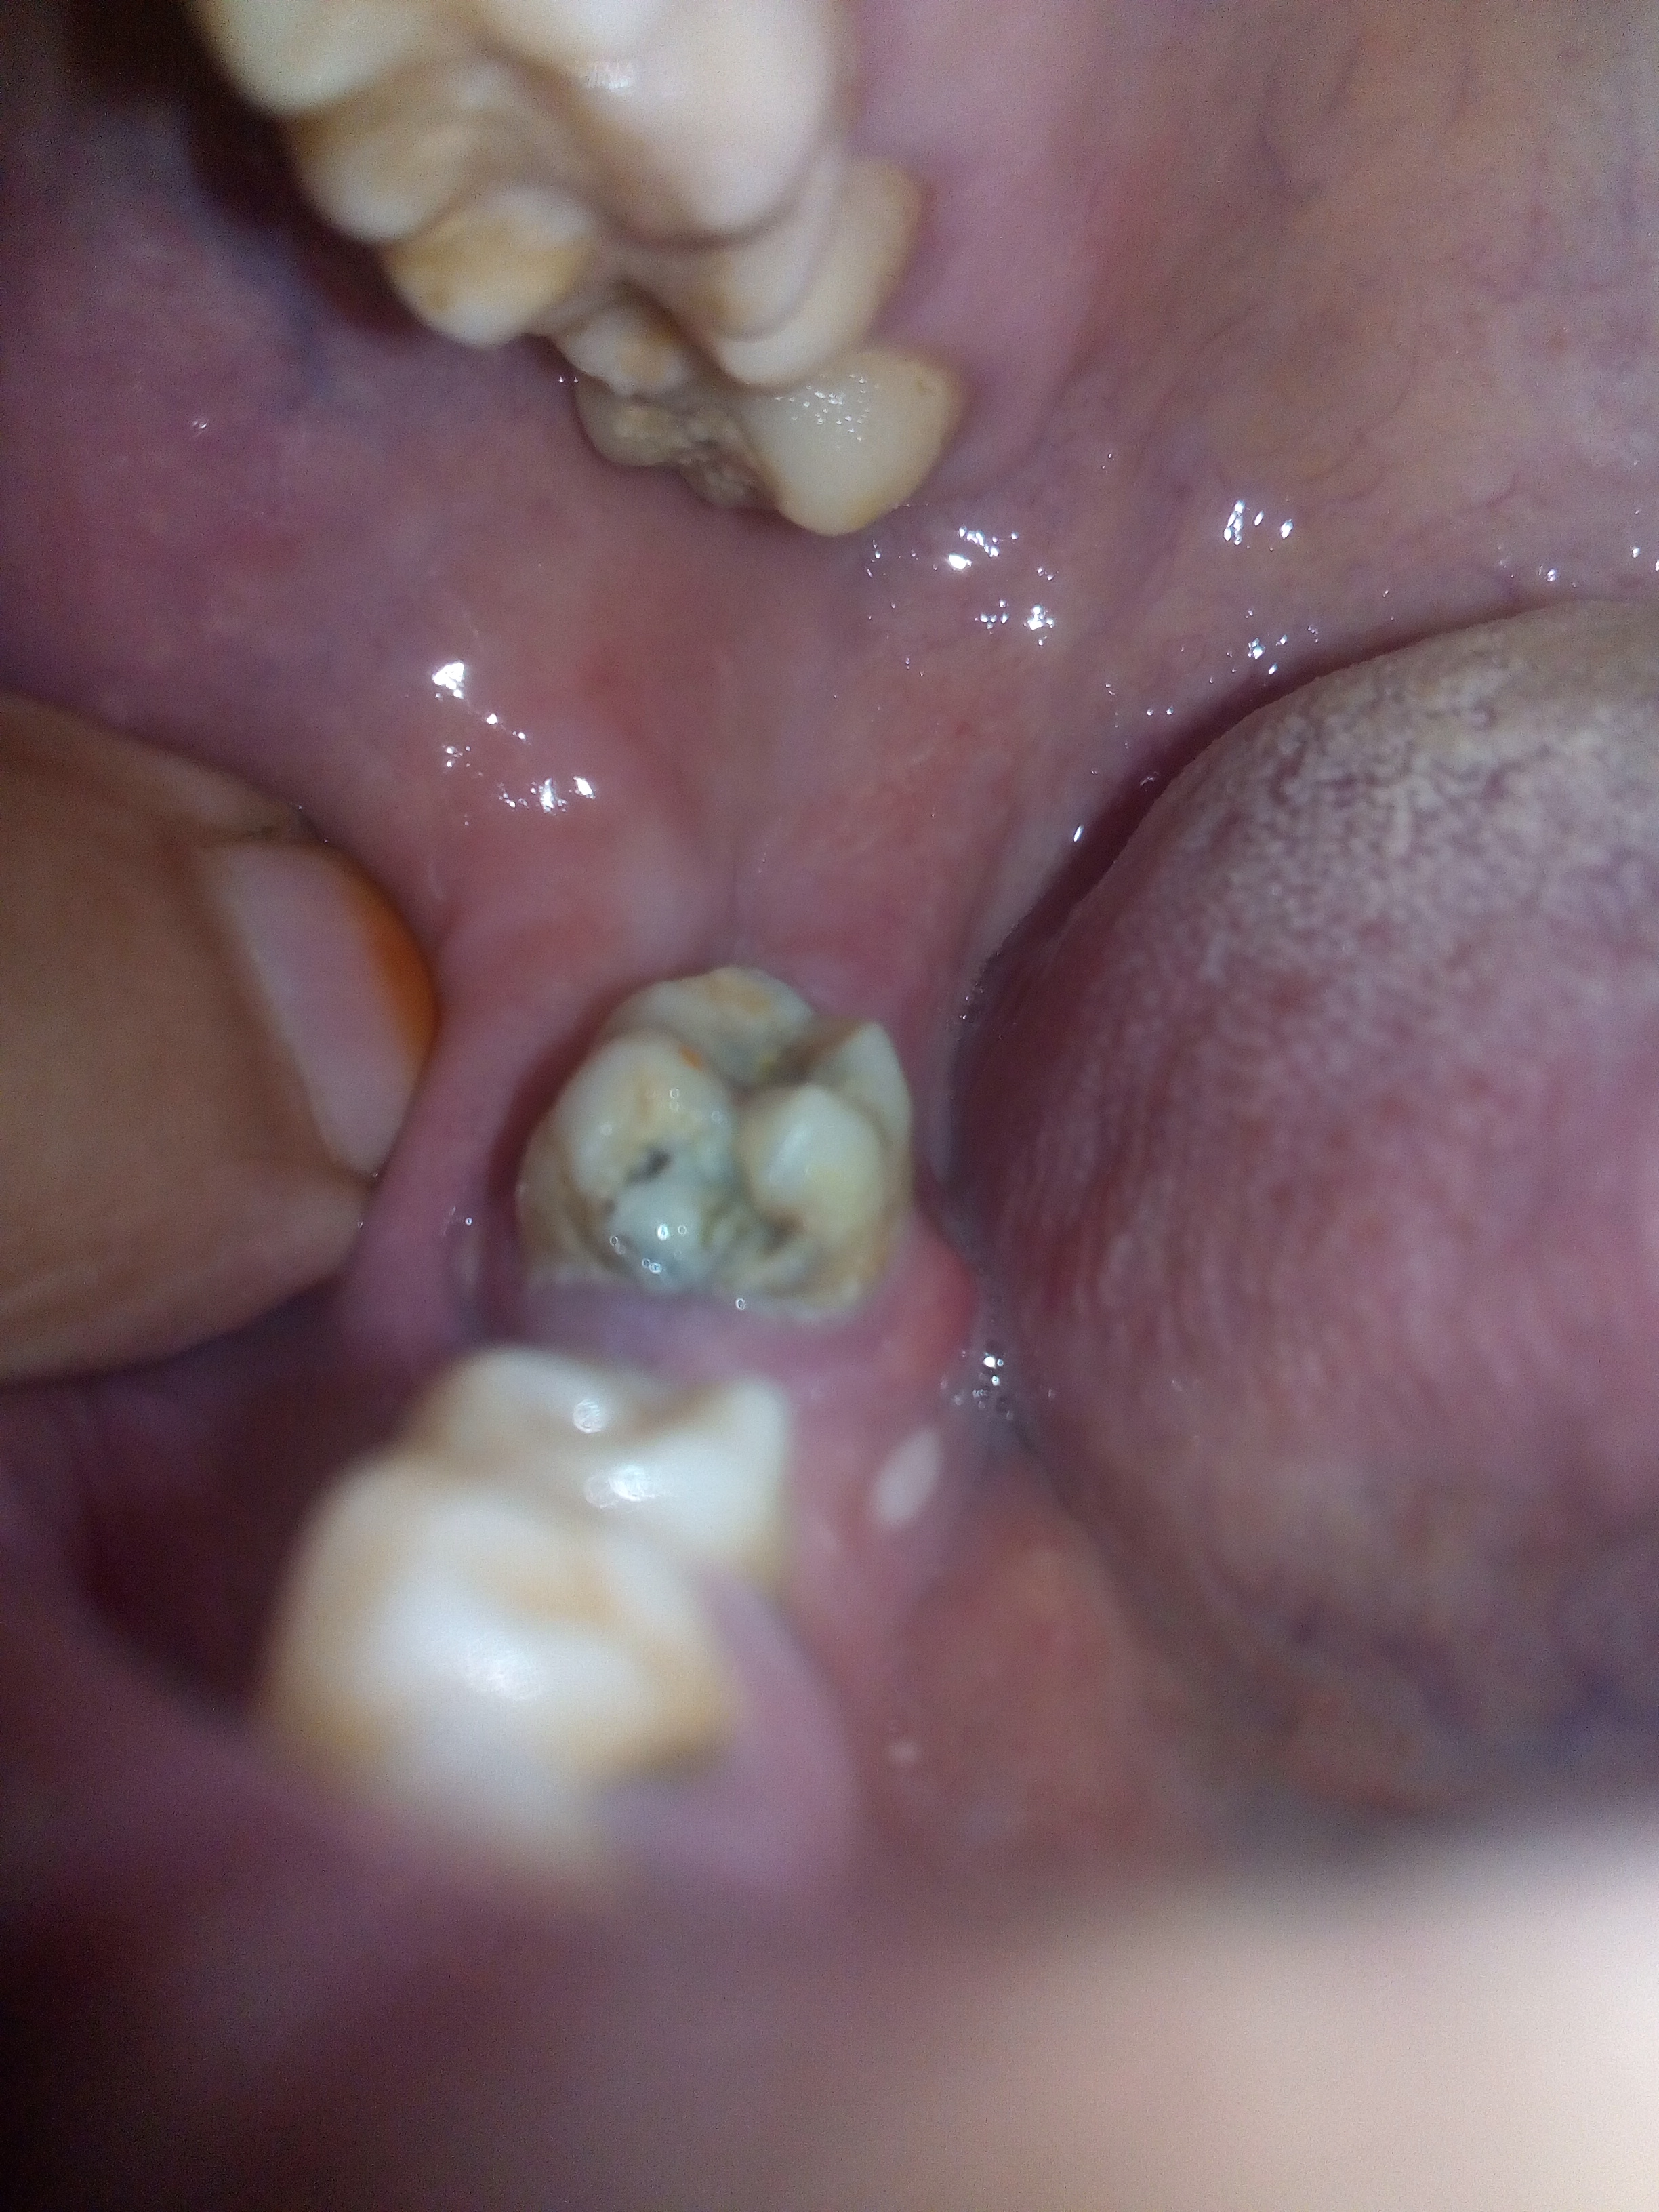

pic of teeth

5 years ago

oral hygiene seems compromised also the tooth is too carious n week

if its possible take her to nearby dentist n get the treatment plan